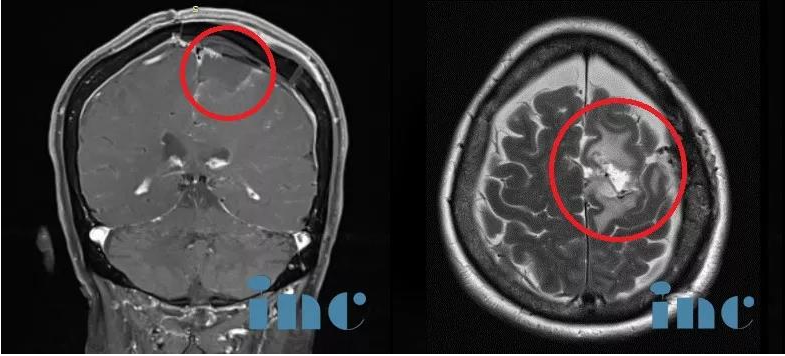

术后情况

手术结果:肿瘤全切、矢状窦成功重建、运动功能区无损伤。术后当天即拔插管,术后1天迁出ICU,术后2天,可以在护理人员搀扶下走路康复训练,术后5天已经可以独自走路,无需陪同,肢体肌力明显好转,术后1周+,恢复地和正常人一样,精神状态很好。

术前MR:脑膜瘤钙化和瘤周压迫、水肿效应明显,且已侵袭矢状窦,压迫运动功能区